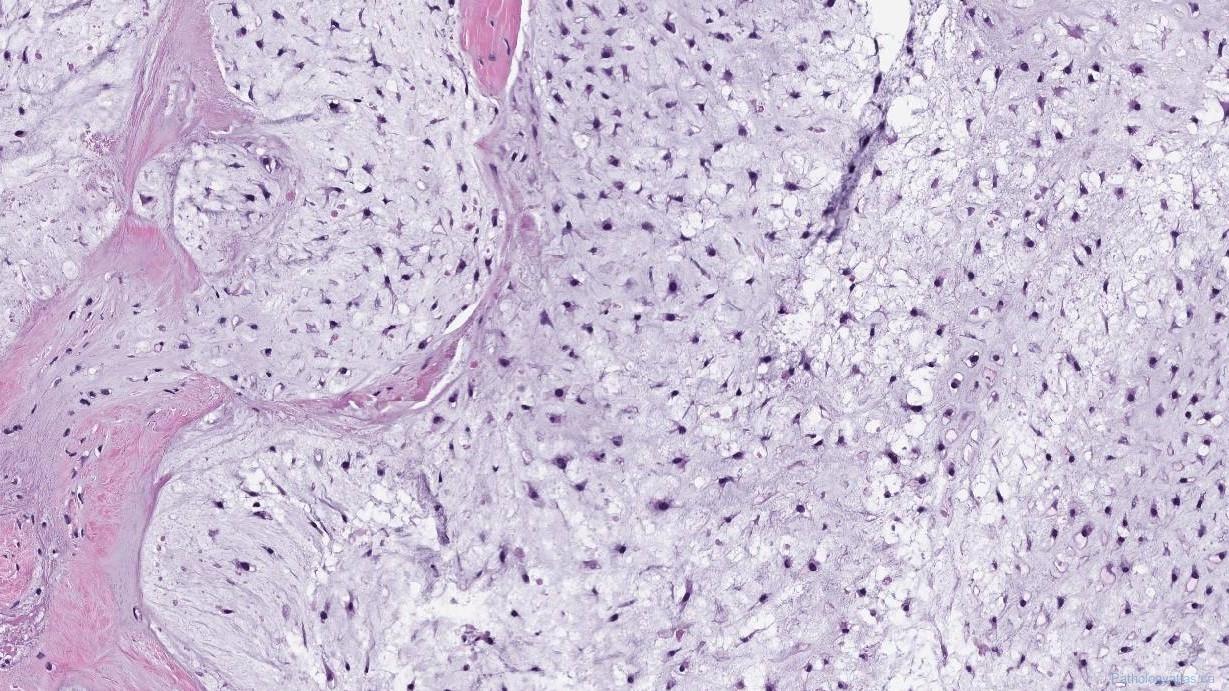

Chondrosarcoma is a rare type of bone cancer that develops in cartilage cells, primarily affecting adults between 20 and 60 years of age. The market for chondrosarcoma treatment has evolved significantly with the introduction of various therapeutic approaches, including surgery, chemotherapy, radiation therapy, and emerging targeted treatments. The complexity of managing chondrosarcoma, coupled...